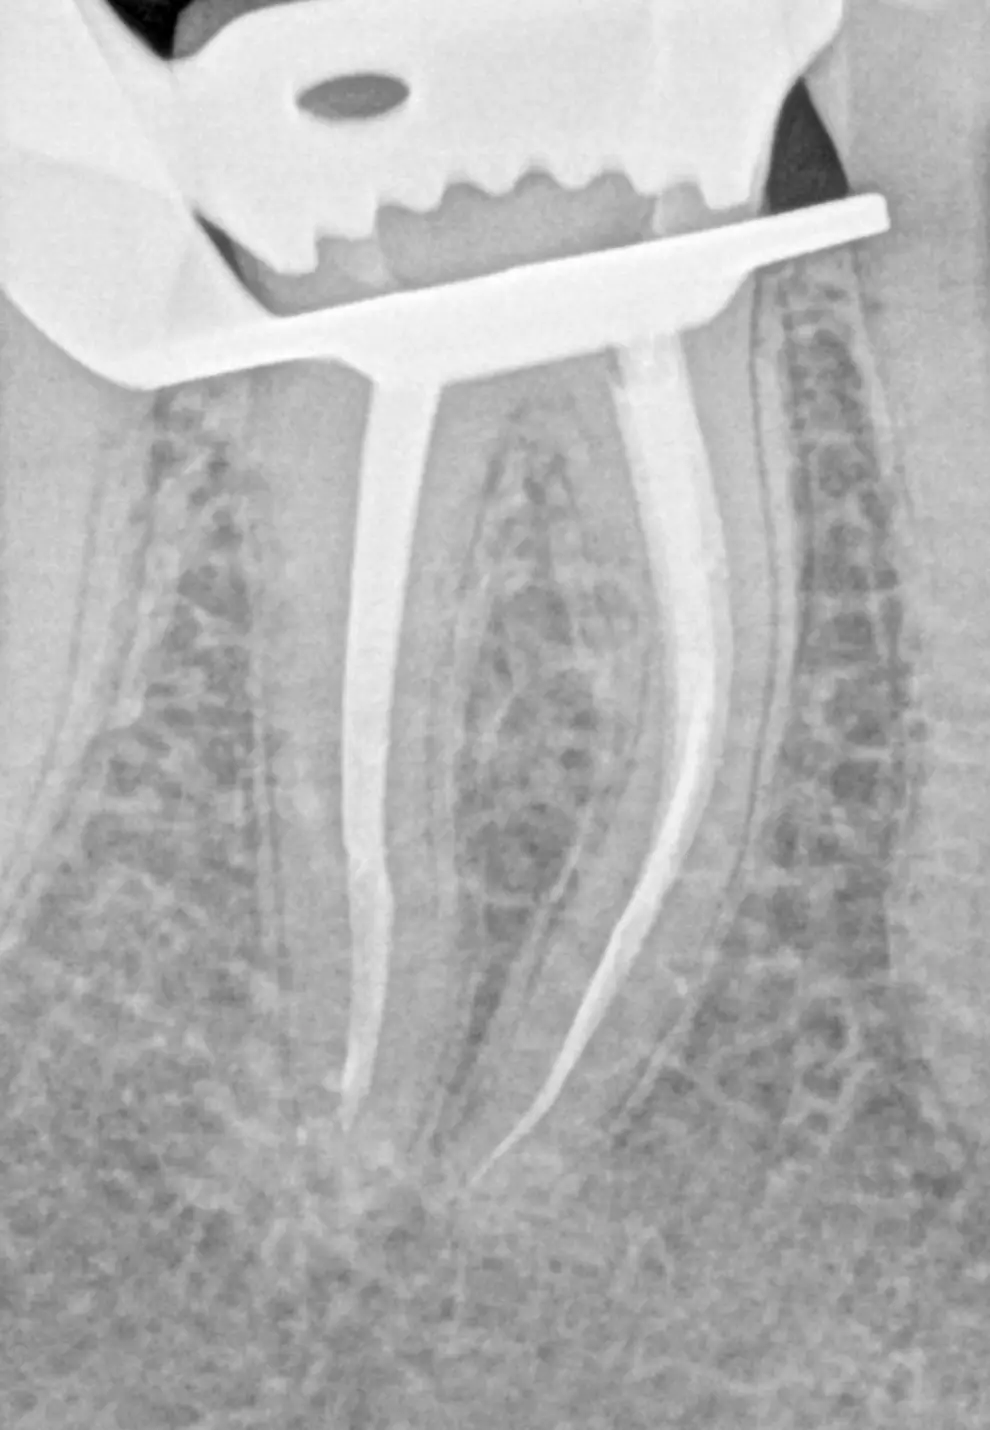

Kanalų valymas mikroskopu

Kanalų gydymas mikroskopu – tai moderni procedūra, leidžianti efektyviai išspręsti danties pulpos uždegimą, vadinamą pulpitų. Mikroskopas padeda labai tiksliai pašalinti pažeistus audinius, atverti visus kanalus ir juos kokybiškai dezinfekuoti. Tai saugus būdas išsaugoti natūralų dantį net ir esant stipriam skausmui ar sudėtingai kanalų sistemai.

Kaip atliekamas dantų kanalų gydymas?

Išsami diagnostika

Atliekama rentgeno ar 3D tomografija, leidžianti tiksliai įvertinti kanalų anatomiją.

Ypač sudėtingi yra krūminiai dantys, todėl kanalų gydymas mikroskopu leidžia tiksliai rasti ir išvalyti visus kanalus.